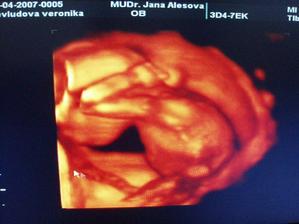

Tak i konečně já přidávám pár svých fotek a postupně budu přidávat další🙂)na prvním utz (fotce) ještě není moc vidět, ale máme srdíčko, jupíííí, zato na druhé už se nám budulínek pořádně ukázal, hip hip hurá🙂))